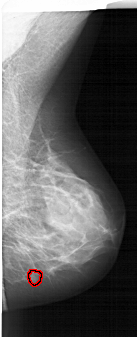

A_1877_1.RIGHT_CC

RIGHT_CC LINES 4966 PIXELS_PER_LINE 2701 BITS_PER_PIXEL 12 RESOLUTION 43.5 OVERLAY

FILE: A_1877_1.RIGHT_CC.OVERLAY

TOTAL_ABNORMALITIES 1

ABNORMALITY 1

LESION_TYPE MASS SHAPE LOBULATED MARGINS CIRCUMSCRIBED

ASSESSMENT 4

SUBTLETY 3

PATHOLOGY BENIGN

TOTAL_OUTLINES 1

BOUNDARY